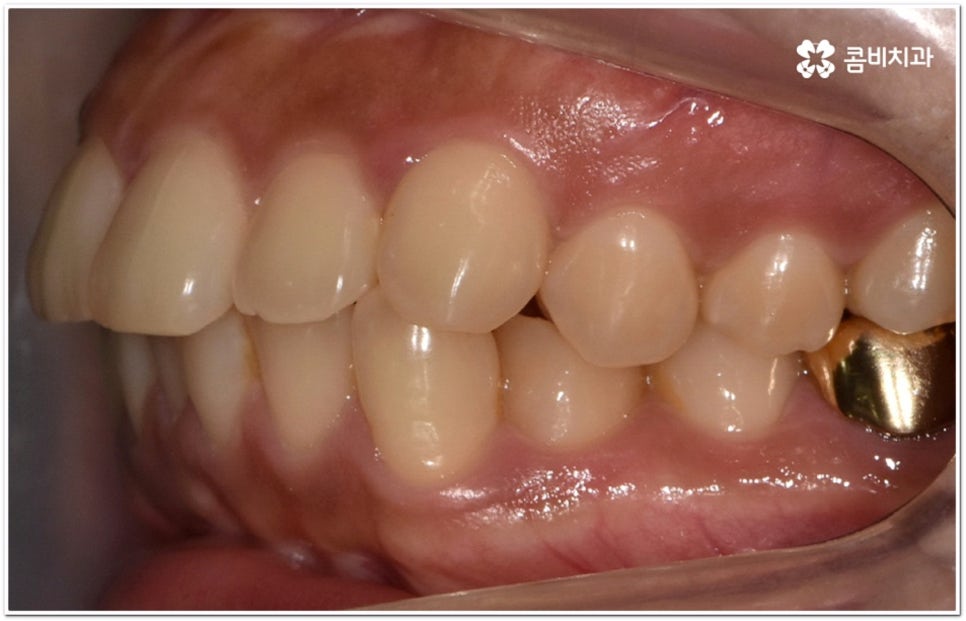

옆에서 봤을 때 코나 턱보다 입이 더 튀어나와 있으면 뾰루퉁한 인상을 줄 수 있고 웃을 때 잇몸이 드러나 콤플렉스처럼 느껴질 수 있는데요. 정도가 심한 경우 입을 꼭 닫고 있기 어려워 자기도 모르게 구호흡을 하게 되면서 여러 구강 질환 및 구취를 유발하게 될 수도 있기 때문에 이러한 심미적 또는 기능적인 이유로 돌출입교정치과 를 알아보시는 분들이 많이 있을 거예요.

이때 위아래 치아가 맞물리는 데는 별다른 문제가 없고 앞니 등 치아가 조금 뻐드러진 상황이라면 각도만 개선해도 되지만 잇몸뼈 자체가 나와 있고 교합에도 문제가 있다면 종합적인 해결이 필요할 수 있는데요.

단순히 치아가 튀어나온 각도를 고친다고 돌출입 개선이 되지는 않고 구조적 골격적인 원인을 파악하여 해결해야 추후 턱관절 건강 부분에까지 좋지 않은 영향을 미치는 것을 막을 수 있습니다.

환자마다 치열, 교합, 치아가 튀어나온 각도, 잇몸이 드러나는 정도, 상악과 하악의 구조 및 관계 등 턱관절 관련 부분 상황이 모두 다르기 때문에 3D CT 같은 정밀 검진 기계를 통해 이를 꼼꼼하게 살펴보고 각각에 맞는 계획을 세밀하게 세워 교정 치료를 진행해 줄 필요가 있어요. 이때 환자분들의 상황에 따라 양악수술과 같은 외과적인 방법을 병행해야 하는 케이스도 있을 수 있기 때문에 돌출입을 가지고 계신 분들 중에서 수술에 부담을 느끼고 지레 치료를 포기하신 분들도 있을 수 있는데 정도가 많이 심각하지 않고 구조적인 원인이 크지 않다면 대부분의 케이스는 치아교정 만으로도 충분히 개선이 가능하니 먼저 돌출입교정치과 에 들러서 정밀 검사를 진행한 후 치료 방향에 대해 의료진과 논의해 보시면 좋을 거예요.